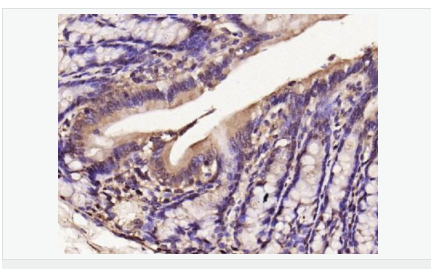

| 英文名稱 | iNos/Nos-2 |

| 中文名稱 | 一氧化氮合成酶-2(誘導型)抗體 |

| 產(chǎn)品應用 | WB=1:500-2000 IHC-P=1:100-500 IHC-F=1:100-500 Flow-Cyt=1μg/Test ICC=1:100-500 IF=1:100-500 (石蠟切片需做抗原修復) not yet tested in other applications. optimal dilutions/concentrations should be determined by the end user. |

| 產(chǎn)品介紹 | Nitric oxide (NO) is an inorganic, gaseous free radical that carries a variety of messages between cells. Vasorelaxation, neurotransmission and cytotoxicity can all be potentiated through cellular response to NO. NO production is mediated by members of the nitric oxide synthase (NOS) family. NOS catalyzes the oxidization of L-arginine to produce L-citrulline and NO. Two constitutive isoforms, brain or neuronal NOS (b or nNOS, type I) & endothelial cell NOS (eNOS, type III), and one inducible isoform (iNOS, type II), have been cloned. All NOS isoforms contain calmodulin, nicotinamide adenine dinucleotide phosphate (NADPH), flavin adenine dinucleotide (FAD), and flavin mononucleotide (FMN) binding domains. Nitric oxide synthase is expressed in liver, macrophages, hepatocytes, synoviocytes, stimulated glial cells and smooth muscle cells. Cytokines such as interferon-gamma (IFN), tumor necrosis factor (TNF), interleukin-1 and -2, and lipopolysaccarides (LPS) cause an increase in iNOS mRNA, protein, and activity levels. Protein kinase C-stimulating agents exhibit the same effect on iNOS activity. After cytokine induction, iNOS exhibits a delayed activity response which is then followed by a significant increase in NO production over a long period of time. Human iNOS is regulated by calcium/calmodulin (in contrast with mouse NOS2). Function: Produces nitric oxide (NO) which is a messenger molecule with diverse functions throughout the body. In macrophages, NO mediates tumoricidal and bactericidal actions. Also has nitrosylase activity and mediates cysteine S-nitrosylation of cytoplasmic target proteins such COX2. Subunit: Homodimer. Binds SLC9A3R1. Tissue Specificity: Expressed in the liver, retina, bone cells and airway epithelial cells of the lung. Not expressed in the platelets. Similarity: Belongs to the NOS family. Contains 1 FAD-binding FR-type domain. Contains 1 flavodoxin-like domain. SWISS: P35228 Gene ID: 4843 Database links: Entrez Gene: 4843 Human Entrez Gene: 18126 Mouse Omim: 163730 Human SwissProt: P35228 Human SwissProt: P29477 Mouse Unigene: 709191 Human Unigene: 2893 Mouse Unigene: 10400 Rat Important Note: This product as supplied is intended for research use only, not for use in human, therapeutic or diagnostic applications. 合成與降解(Synthesis and Degradation) 催化生物體內(nèi)一氧化氮(NO)生成的酶。分神經(jīng)型一氧化氮合成的酶(nNOS or NOS-1)、誘導型一氧化氮合成的酶(iNOS or NOS-2)、內(nèi)皮型一氧化氮合成的酶(eNOS or NOS-3)。 |